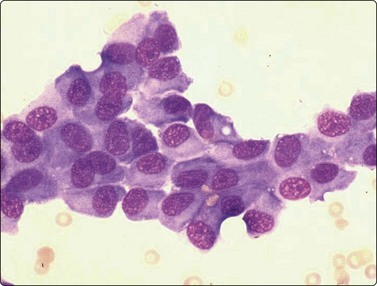

In atypical ES and PNET the cellular and nuclear atypia is more marked than in conventional ES. Rosette-like structures are more common and the distinction between large light and small dark cells less obvious, especially in PNET, and cells with thin cytoplasmic processes as well as rhabdomyoblast-like cells are present (Fig. 16.32).

image image

Fig. 16.32 ES/PNET family of tumors

Distinction between large light and small dark cells less obvious in PNET than in conventional Ewing’s, and cells with thin cytoplasmic processes (A) and rhabdomyoblast-like cells (B) are present (A, MGG, HP; B, H&E, HP).